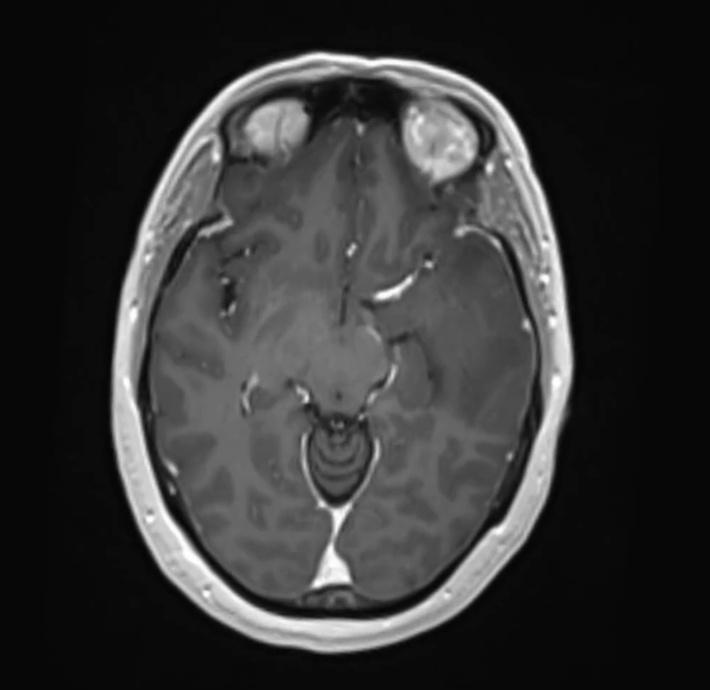

Now, imagine walking into this same house and immediately turning the lights on. Suddenly, everything is clear, and you can see each object and obstacle in the room. This is like seeing your anatomy in three dimensions. Now envision this same scenario as a doctor performing surgery. No two brains are alike, and working with a full 3D rendering means the house lights are on bright.

Enter the world of 3D surgery—a revolution that promises to bring the same richness and depth of our three-dimensional world into the operating room. With 3D imaging and surgical techniques, surgeons are no longer confined to flat representations. They can see the human body in its true form, with all its intricacies and details. This not only enhances their understanding but also empowers them and their patients to make more informed, precise decisions.

But the advancements don’t stop there. Surgeons are not only using these premier, patient-specific images in the clinic and for surgical planning but are also bringing them into the operating room for enhanced intraoperative visualization. This real-time, immersive detail allows surgeons to navigate complex procedures with unparalleled accuracy and confidence. At Surgical Theater, our mission is to deliver your 3D world throughout the patient’s entire continuum of care—from the patient’s consultation and surgical planning to the procedure itself. Imagine your surgeon practicing your surgery with this colorful rendering before entering the OR, transcending visual limitations and achieving a level of preparedness and precision that was previously unimaginable.